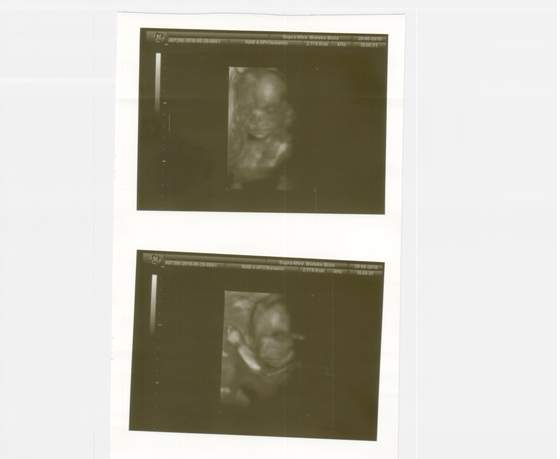

Fanka BB :)

Coraz większe i ładniejsze maleństwa

Ja niestety muszę do tego 17 maja wytrzymać, żeby dostać fotkę w końcu, bo jedną mam ale to 11tydzień był....... a tu teraz takie cuda są